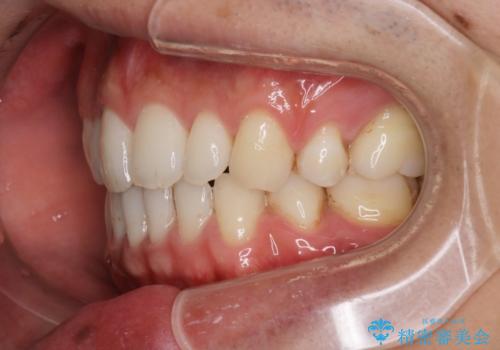

前歯の隙間を閉じたい 口元も下げたい ハーフリンガルによる抜歯矯正

- 上の前歯の隙間と口元を下げたとのことで来院されました。

上顎正中離開と、口唇の突出感がありました。

上下左右の歯を1本ずつ抜歯しして、上顎の前歯を後方に移動させるのと、正中の隙間を閉じる計画としました。

抜歯をせず上顎の正中離開のみの矯正もできましたが、患者様と相談して口元の改善も同時に行うために抜歯矯正の計画としました。